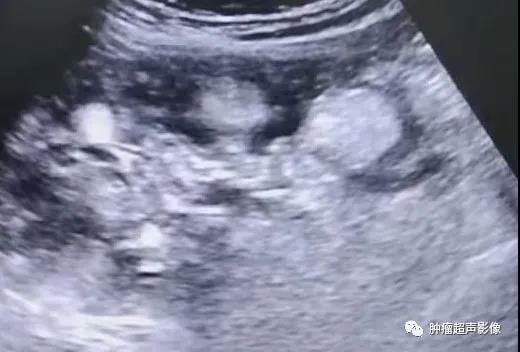

超声检查发现双肾多发AML,尤其是肿瘤数目较多、瘤体较大、肾脏轮廓不清时要想到TSC的可能,并询问相关病史,并观察面部、建议颅脑CT检查等。肾囊肿在TSC中也较常见,是该病临床诊断的次要指征。肝AML在超声上与血管瘤表现类似,均表现为大小不等圆形或椭圆形偏强回声团块,肝AML含有脂肪成分,回声比血管瘤回声更强一些,结合TSC病史,肝脏多发偏强回声占位应首先考虑为AML。

体检发现双肾多发错构瘤,双肾密集分布,考虑结节性硬化症表现,建议头颅检查(病例由江口县人民医院胡海英医师提供)

女,61,因肾肿瘤入院治疗,超声及CT示两肾多发错构瘤,建议头颅检查。